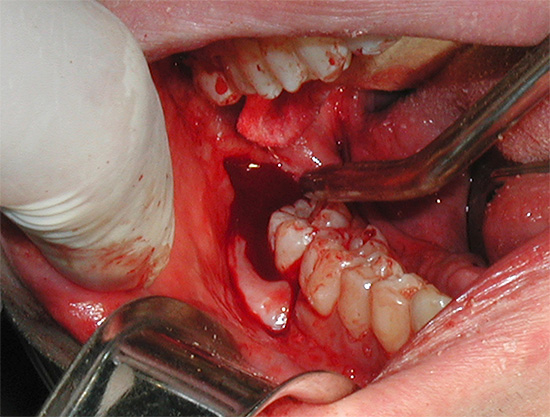

De particular perigo é a longa cicatrização das gengivas no contexto da infecção após extração do dente do siso inferior. Como os dentes inferiores da sabedoria são cercados por tecidos moles com suprimento sanguíneo abundante, as bactérias que entram na ferida após a remoção simples ou, principalmente, complexa podem levar a sérias conseqüências, até espalhar a infecção profundamente nos tecidos. A infecção da mandíbula e das áreas periomandibulares em um contexto de imunidade reduzida pode levar a abscessos com risco de vida e fleuma.

A expressão extrema dessas complicações é a sepse - infecção do sangue com flora microbiana patogênica, que pode levar à morte.